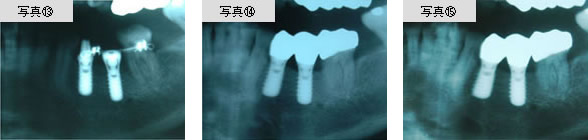

インプラントを固定源としたスプリングによって広がったスペースに、もう一本のインプラントを植立しました。(写真13参照)

また、倒れこんでいた歯のまわりの骨が再生しました。(写真15参照)

かつては抜歯が必要だった症例でも、インプラント治療や骨再生治療によって、抜歯を回避できるようになっています。当院では、「将来に歯を残したい」「健康な歯に負担をかけたくない」という方に、インプラント治療を選択肢の一つとしてご提案しています。